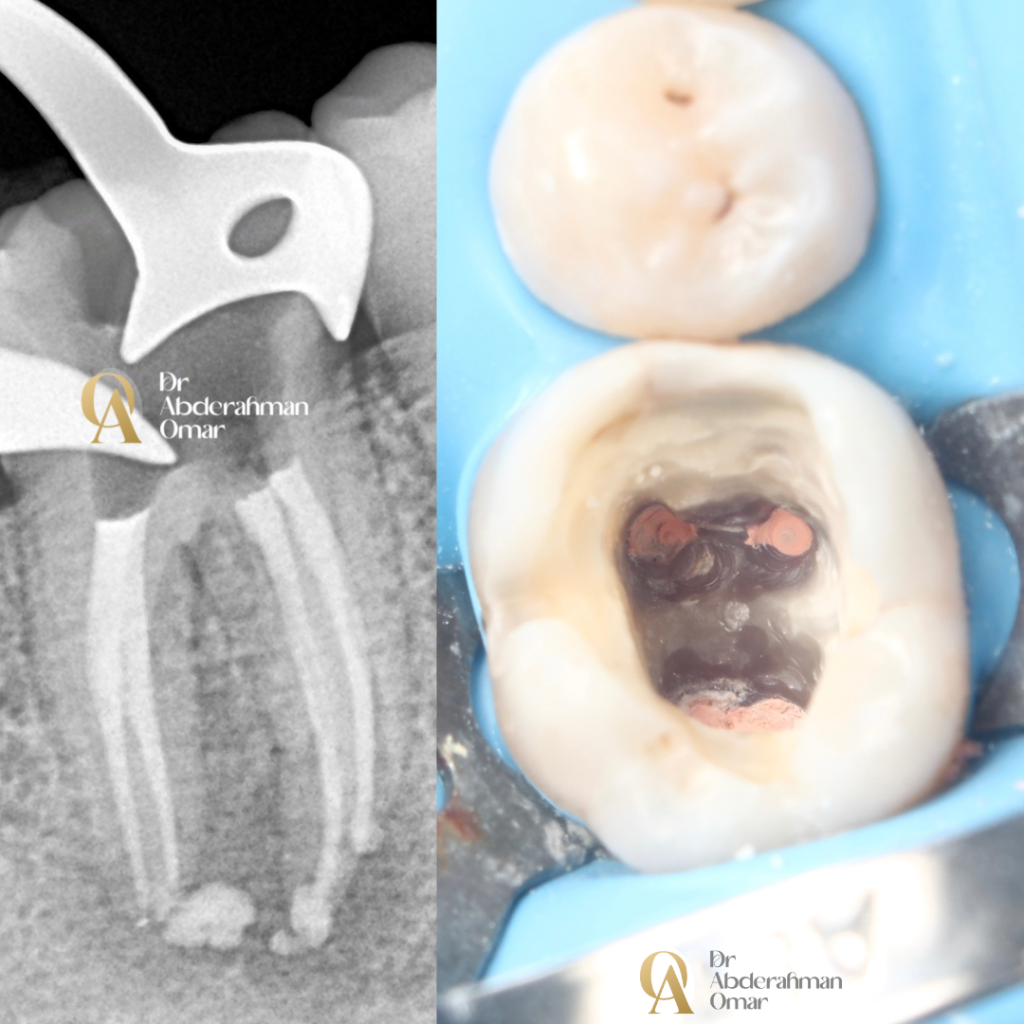

This case was a 15 years old patient presented with chronic apical abscess with mandibular first molar involved a previously root canal-treatment that presented with symptomatic failure and a defective amalgam restoration. The diagnostic radiograph showed inadequate obturation with 3 canals, one missed canal and signs of apical pathology.

1. Rubber dam isolation, Removal of old amalgam and gutta-percha, followed by thorough irrigation and disinfection of the canal system.

2. Microscopic retreatment performed to ensure complete debridement and shaping of the canal space.

3. Obturation achieved with warm vertical condensation technique